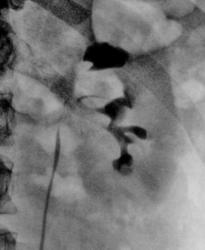

"Перво-наперво" предположу наличие кисты (объёмного образования) в правой почке...

Да, Валентин Львович, у меня тоже такие же мысли были, справа точно есть объёмное образование или в верхнем полюсе или в синусе почки, слева так же наличие признаков парапельвикальной кисты, верхняя и нижняя группа чашек оттеснены, несколько сдавлены, но после того как сделали УЗИ, все сомнения почему то у урологов исчерпались, по УЗИ как обычно всё ровно и чётко, так что парень пошел справлять новый год домой, буду уповать на назначение поликническим урологом МСКТ-забрюшинного пространства.

Но ведь есть оттеснение верхней группы чашечек латерально и лоханка как то оттеснена каудально, Вы так не считаите?

Молодцы ребята узисты! Слева лоханка не контрастирована, но "норма", а что там вместо лоханки слева?

Ежели УЗИ-сты отличные парни, то надо будет объяснить "только полосочки" вместо контрастированной лоханки левой почки.

Так и на 14 минуте слева картиночка интересная. Не контрастируется лоханка.

Так и на 21 минуте лоханки не видно, полосочки какие-то и все...., да и "шейки" чешечек какие-то ... не того или может быть "стойкий спазм шеек чашечек ?

С узистами все ясно - парапельвикальную кисту слева и парапельвикально-каликальную кисту справа они (наверняка) приняли за ампулярного типа лоханки. Но что по КОНКРЕМЕНТУ - в н\трети правого мочеточника на фоне контраста?????